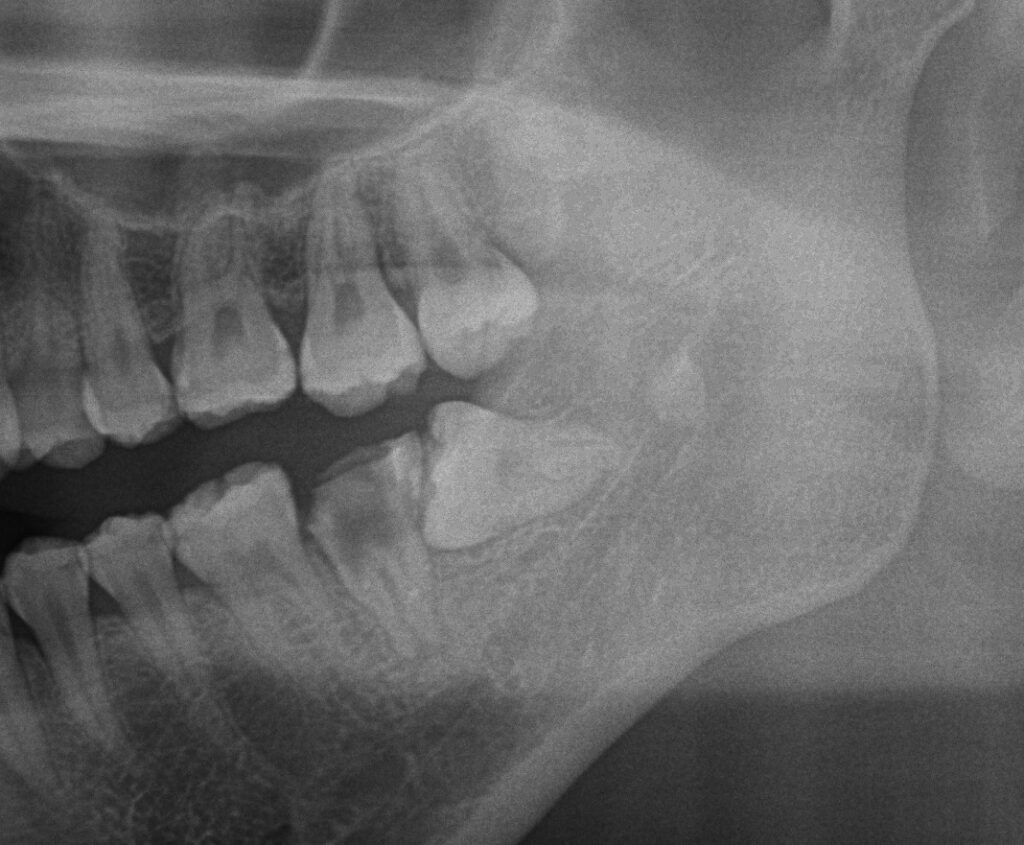

このレントゲンは術前のレントゲンで左下7番目の歯がボロボロで保存不可能なため抜歯をして左上8を左下7の部位に移植する計画を立てました。